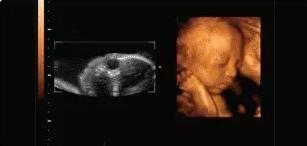

本宝宝有些困了——打哈欠

【在妇产科医院,你可以看到这样的胎宝】